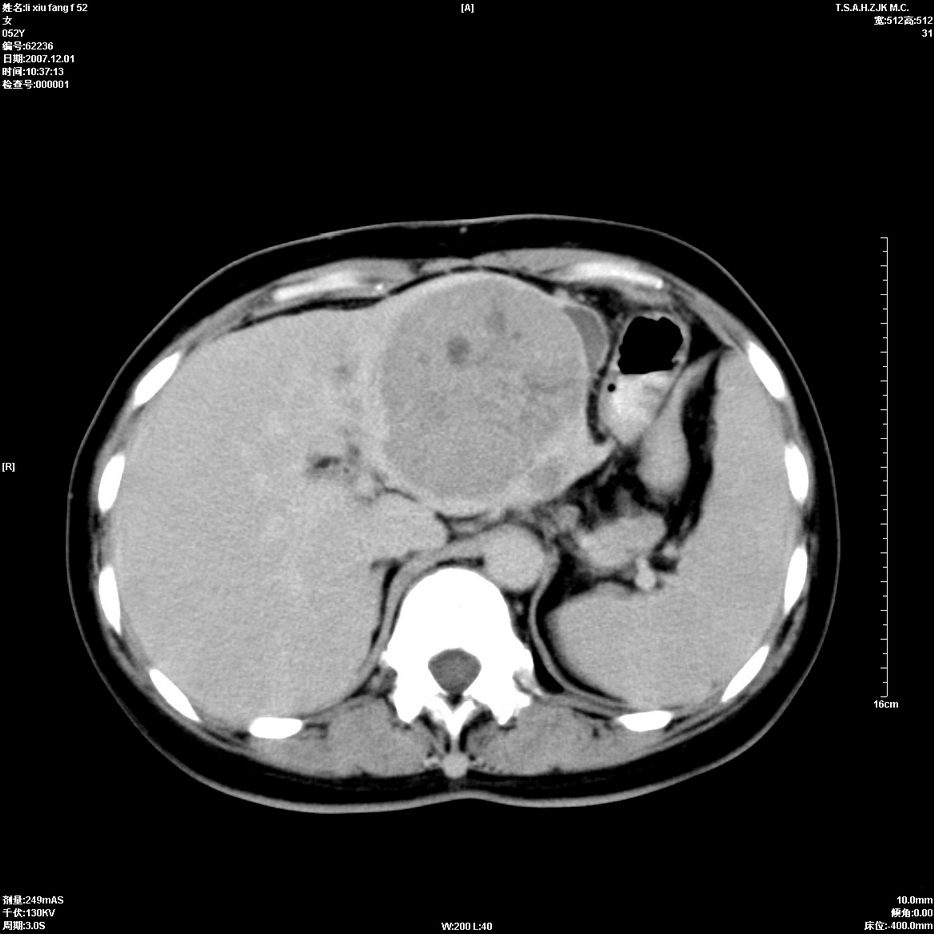

标题: CT12858:女,52岁,胎甲球蛋白861肝左叶占位,肝癌。下腔静 [打印本页]

标题: CT12858:女,52岁,胎甲球蛋白861肝左叶占位,肝癌。下腔静

肝左叶巨大低密度灶肿块,增强符合快进快出表现,有动静脉交通支;静脉期,下腔静脉内有充盈缺损,afp明显升高,支持肝癌并下腔静脉癌栓形成。

以下是引用拾荒者在2008-4-15 22:57:00的发言:[br]肝左叶巨大低密度灶肿块,增强符合快进快出表现,有动静脉交通支;静脉期,下腔静脉内有充盈缺损,afp明显升高,支持肝癌并下腔静脉癌栓形成。